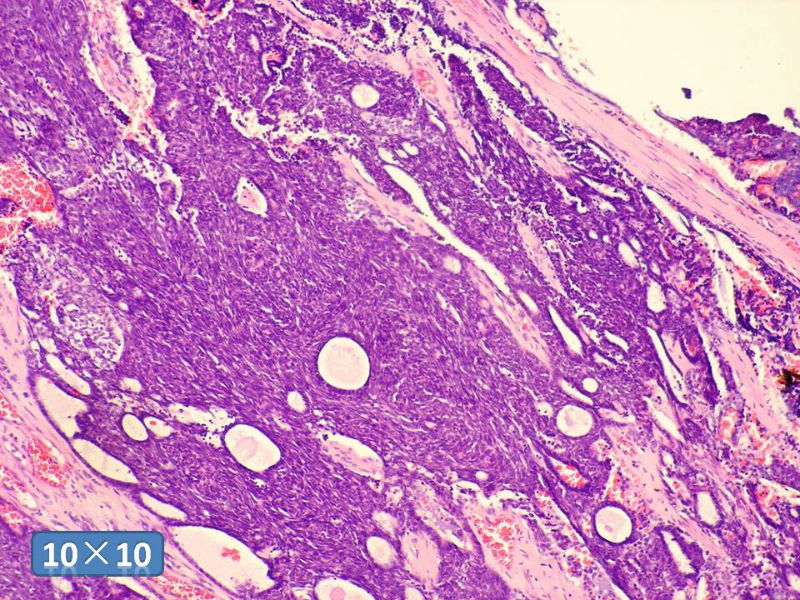

男性,49岁,间断左鼻腔出血3个月。

标签:是嗅母么?

感觉要排除畸胎癌肉瘤。

间质为恶性梭形细胞成分,其间感觉是腺体,两种成分密切相关....

支持嗅神经母细胞瘤(伴有腺体分化)

有上皮和间叶2种结构,畸胎性癌肉瘤是要考虑一下的吧!